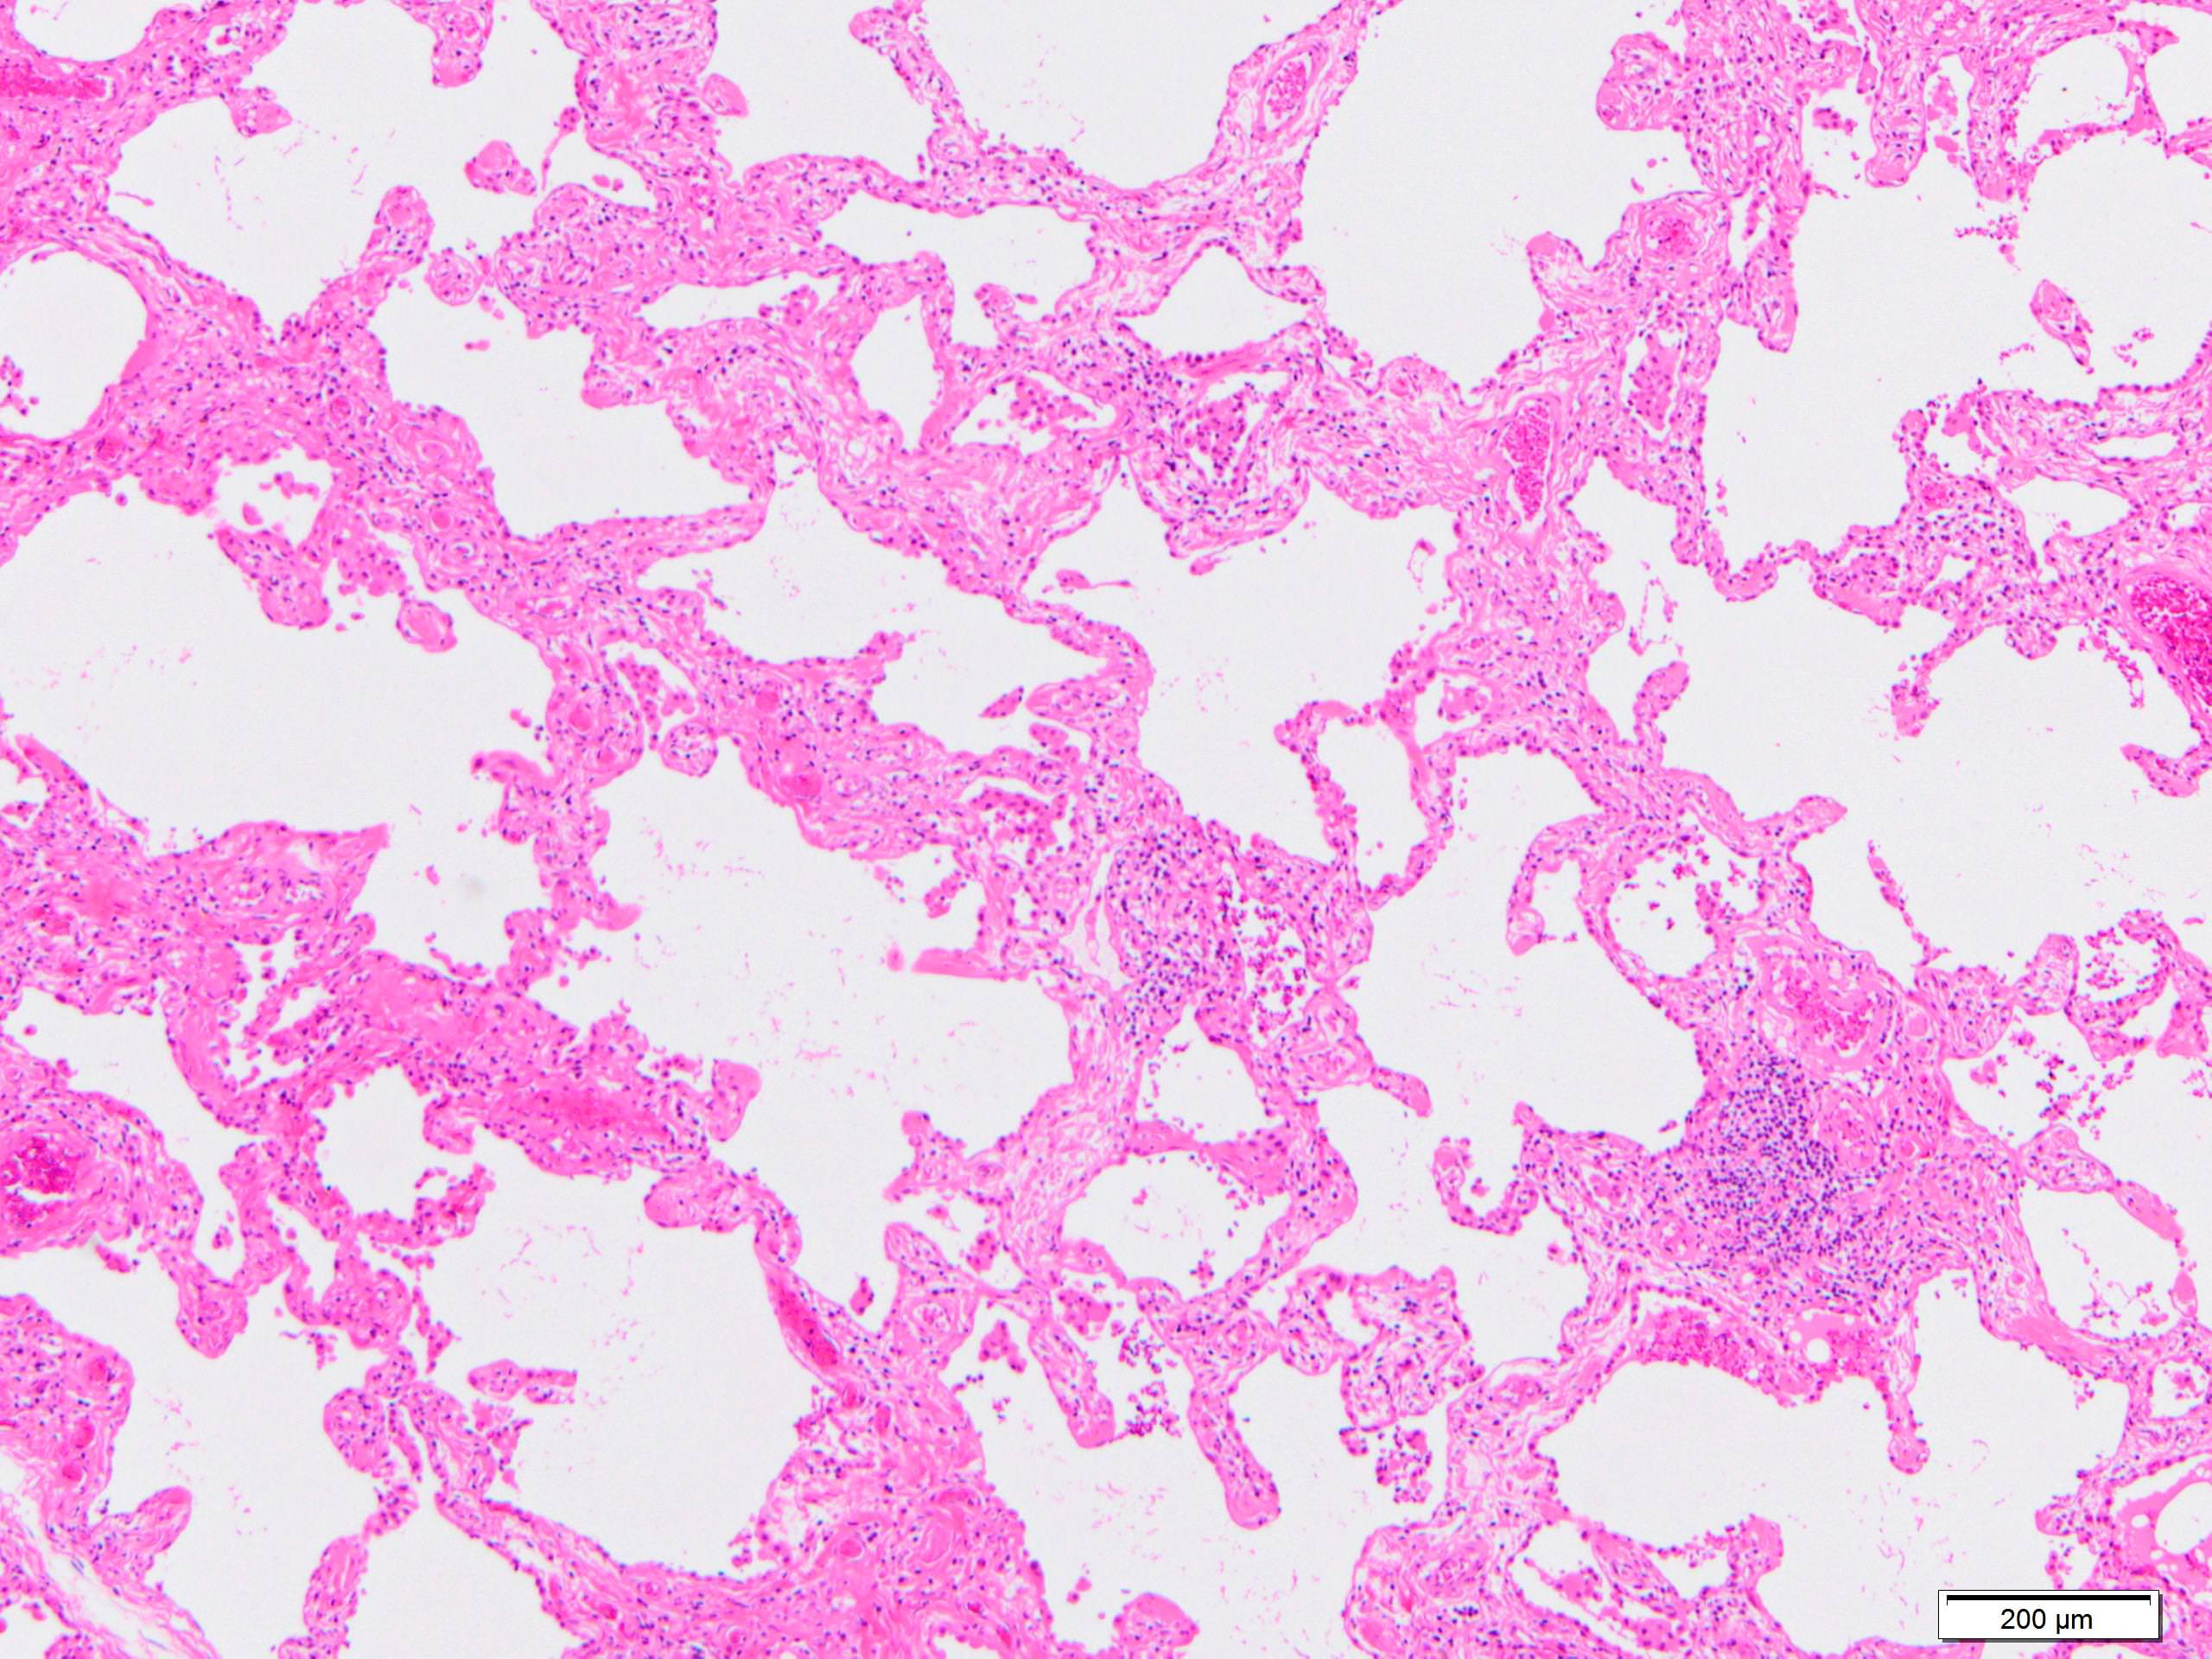

Microscopic (histologic) images

Scroll to see all images.

Contributed by Akira Yoshikawa, M.D.

- Since there are few specific findings for NSIP pattern, it is essential to exclude other lung diseases on histology (Am J Respir Crit Care Med 2008;177:1338)

- Characteristic findings of NSIP pattern

- Diffuse and uniform inflammation ("temporal homogeneity") on low power of alveolar wall, bronchovascular bundles and pleura

- There are usually no normal alveolar walls in the affected lobules

- Cellular or fibrotic change

- Lymphocytic or plasmacytic infiltration

- Loose fibrosis

- Lung architecture is frequently preserved

- "Cellular NSIP" or "fibrotic NSIP" can be stated specifically in pathologist report

- Diffuse and uniform inflammation ("temporal homogeneity") on low power of alveolar wall, bronchovascular bundles and pleura

- Features of interstitial pneumonia with autoimmune features (IPAF) (Chest 2010;138:251):

- Lymphoid aggregates with germinal center

- Extensive pleuritis

- Prominent plasmacytic infiltration

- Dense perivascular collagen

- It is quite rare to see pure NSIP on histology - typically there are focal findings of other interstitial lung disease (Histopathology 2014;65:549)